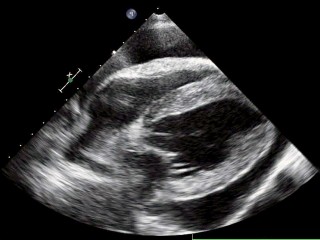

Echografie hart

Toen onze oude echoapparaat vervangen moest worden hebben we ervoor gekozen dat bij ons nieuwe echo apparaat het ook mogelijk moest zijn om echo onderzoeken van het hart te maken. Er moet dan o.a. doppler opzitten en je moet een ECG kunnen aansluiten, ook zijn de eisen voor de kwaliteit veel hoger. Onze nieuwe Mindray M9 voldoet aan deze eisen en heeft een zeer gevoelige en nauwkeurige echo detectie.

De redenen om een echo van het hart te maken zijn divers. Vaak worden er hartecho’s gemaakt om te screenen op erfelijke hartafwijkingen. Bijvoorbeeld wanneer bij een bepaald ras een hartspierziekte voorkomt en men een nestje wil fokken, kan met de echo bekeken worden of het dier op dat moment vrij is. Deze onderzoeken worden niet bij deze praktijk uitgevoerd, maar worden uitgevoerd door dierenarts-specialisten.

De andere indicaties voor een hartecho zijn:

een hartruis - een aritmie - een gallop ritme - verminderde hartgeluiden - hoesten / benauwdheid zonder duidelijke oorzaak

Dierenarts Rianne Compagner maakt de hartecho's, zij heeft diverse cursussen en nascholingen hiervoor gevolgd.

Het hart in beeld

Hieronder zie je een aantal foto's van het hart.